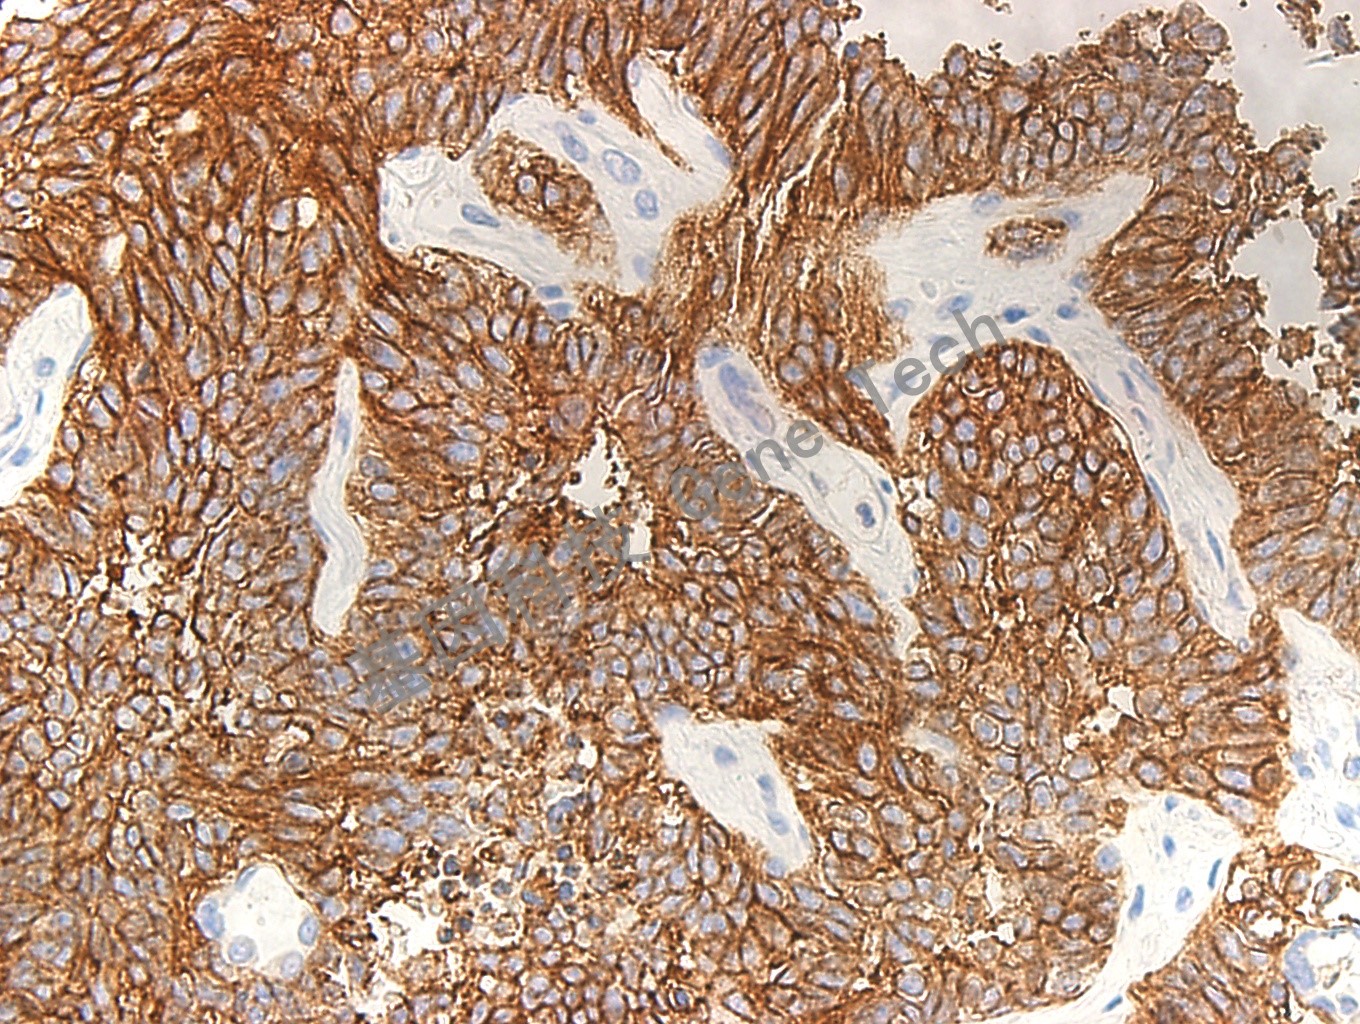

| 克隆號:123C3 | 陽性對照:小細(xì)胞肺癌 | 陽性部位:細(xì)胞膜 |

| 預(yù)處理:高pH熱修復(fù) | 適用:石蠟切片/冰凍切片 | 顯色系統(tǒng):GTvisionTM |

| 簡介:CD56 是一組相關(guān)的細(xì)胞表面糖蛋白,在胚胎發(fā)育以及神經(jīng)細(xì)胞的相互聯(lián)系中發(fā)揮重要作用。CD56 抗原主要表達(dá)于神經(jīng)元、星形細(xì)胞、施萬細(xì)胞、NK 細(xì)胞和小部分活化的T 細(xì)胞。該抗體常用于神經(jīng)外胚層腫瘤、小細(xì)胞肺癌和NK 細(xì)胞淋巴瘤的診斷及研究。 | ||

| 肺癌石蠟切片,用 CD56(GT2005)染色,細(xì)胞膜陽性,DAB 顯色。(40×) | ||